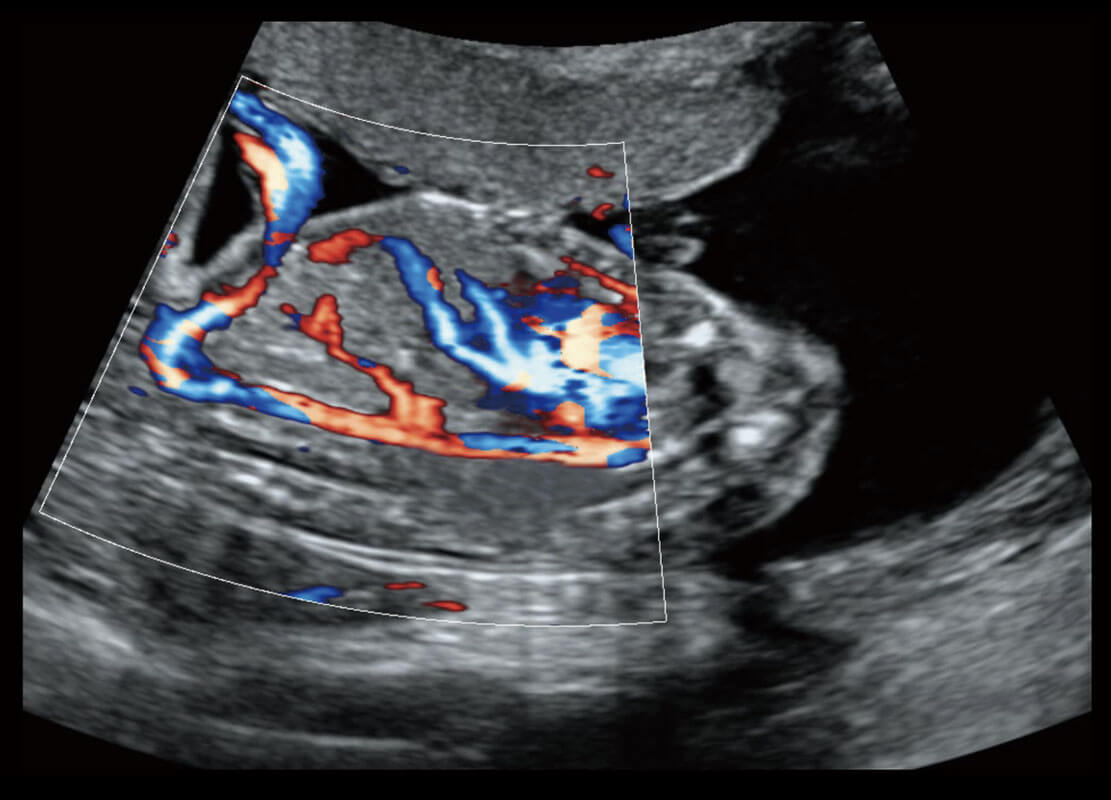

P60搭载一系列胎儿心脏成像技术,实现精细的胎儿心脏评估。

• 四腔切面

• 四腔心血流

• 右室双出口

• 胎心容积成像